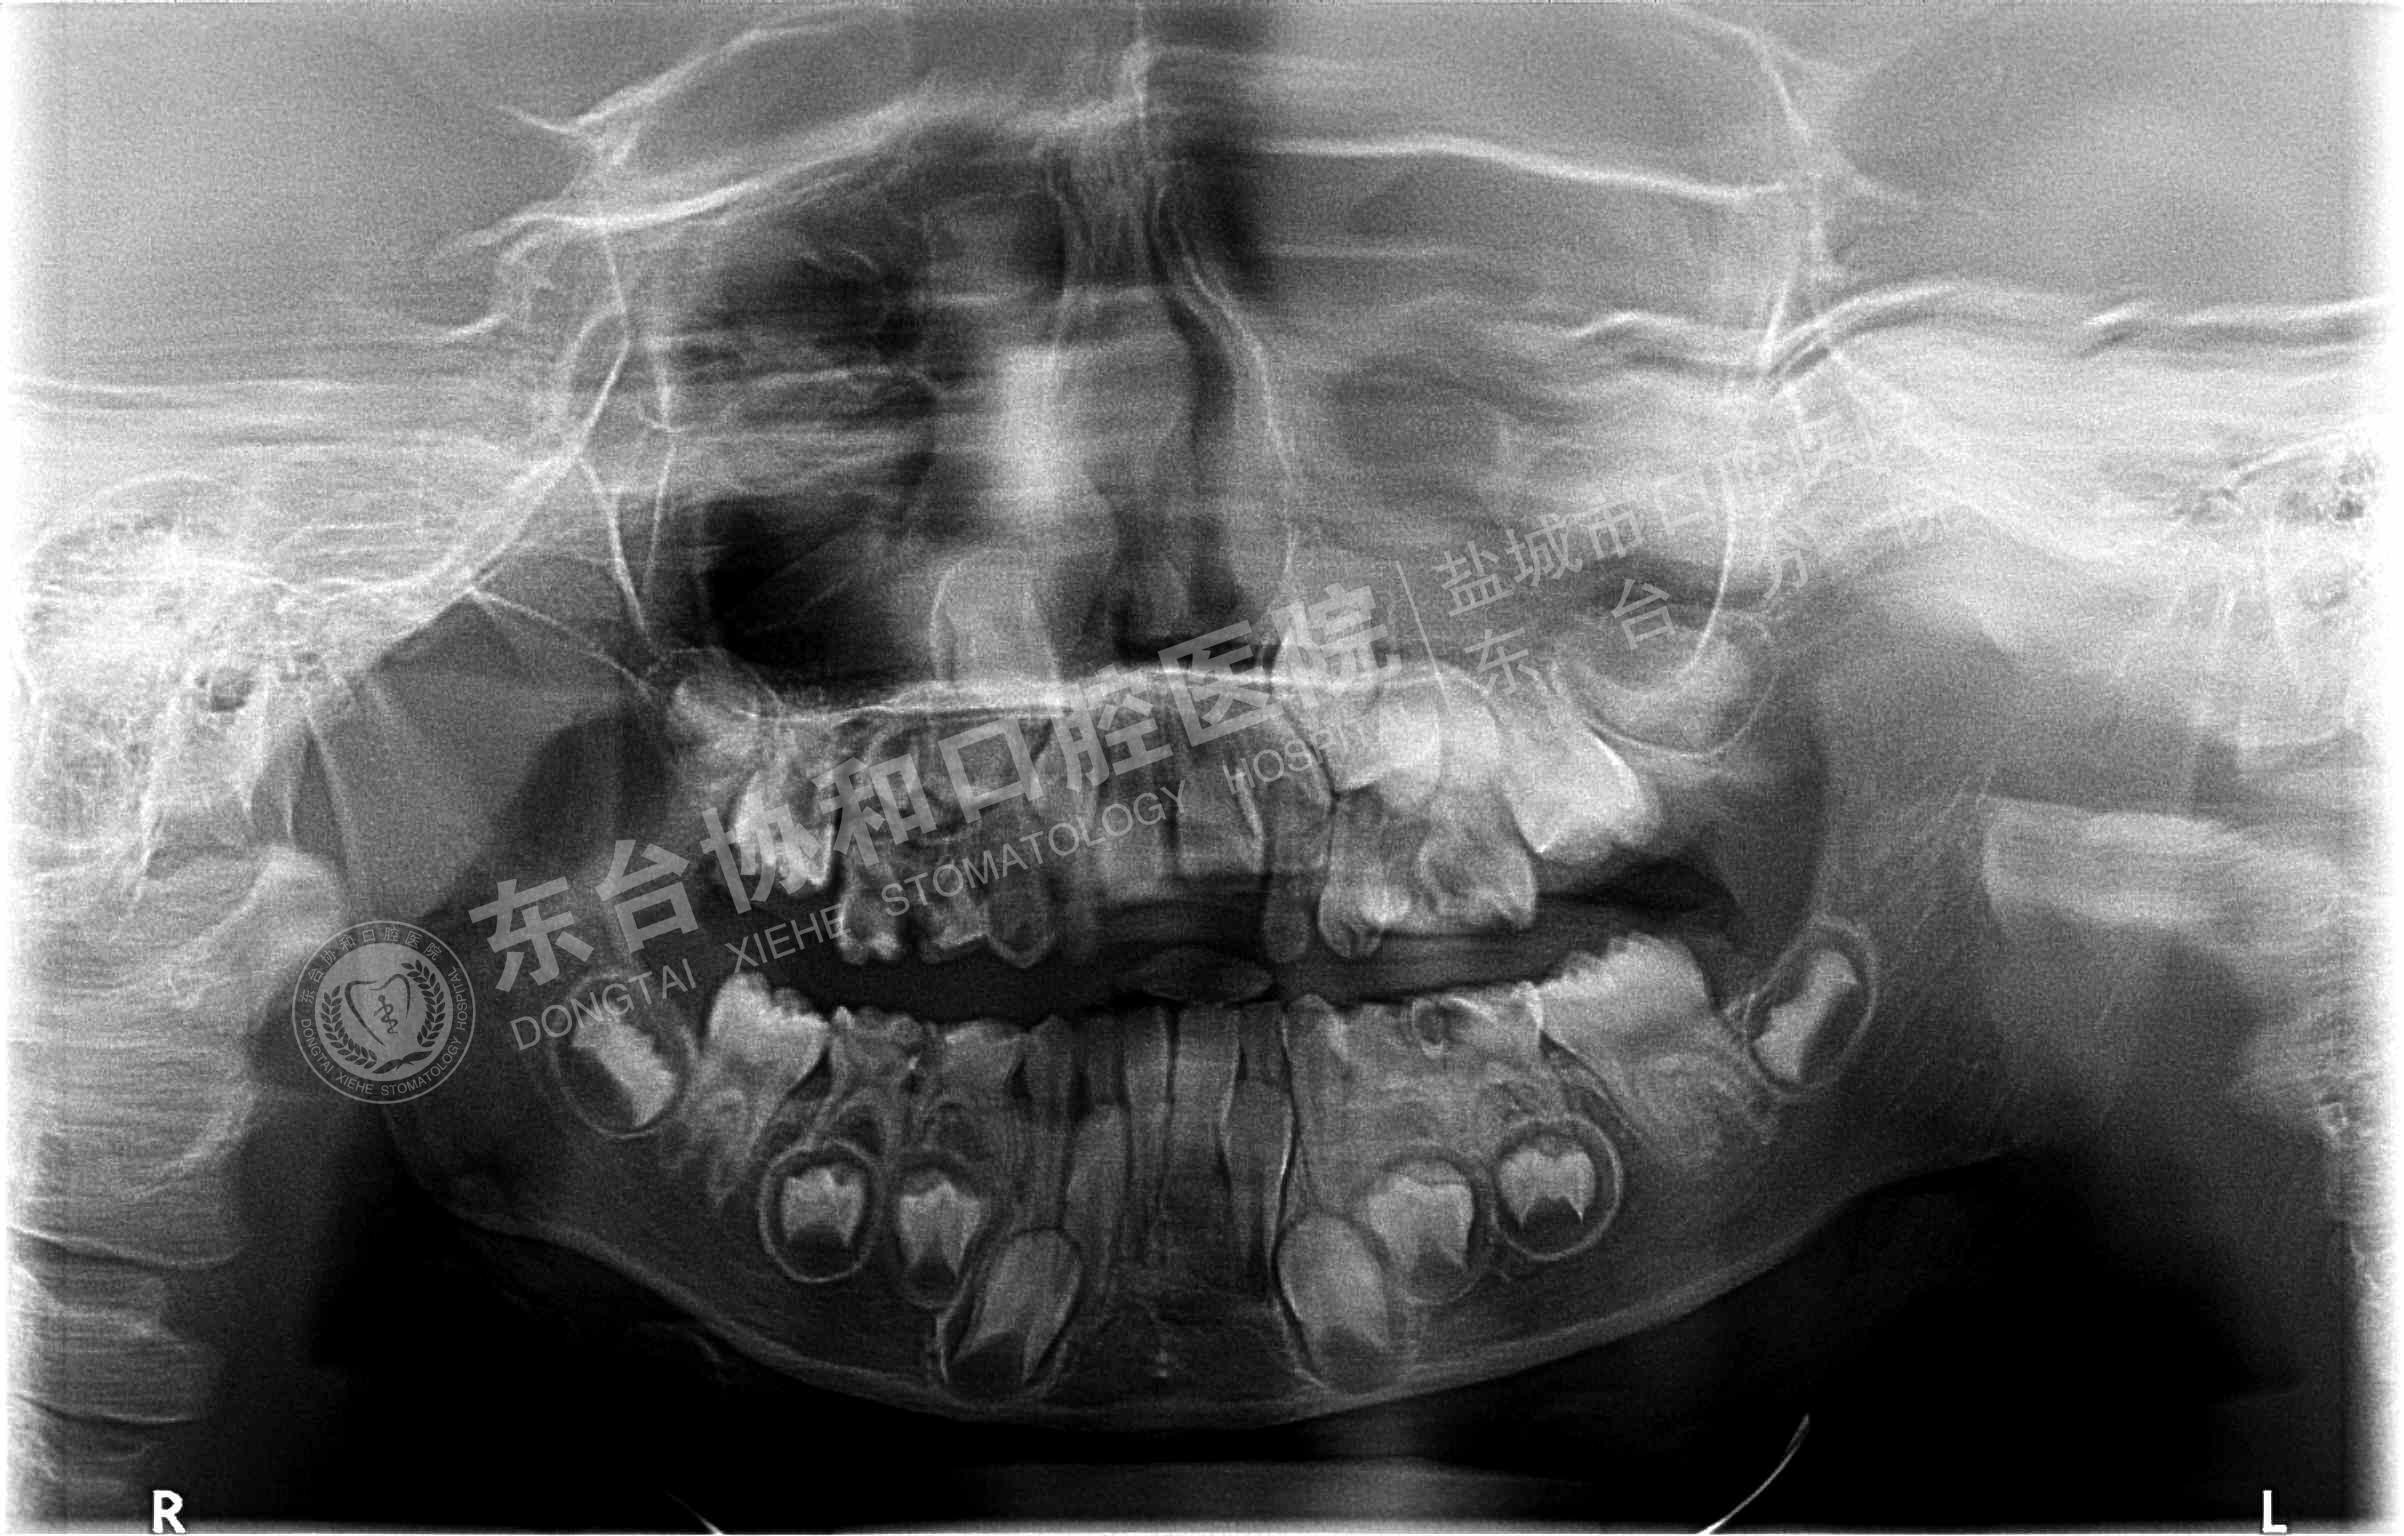

很多患者都很排斥拍牙片,認(rèn)為醫(yī)院是為了多收錢才讓他們拍的,其實(shí)這是一個(gè)錯(cuò)誤的想法,拍牙片是口腔科常用重要的檢查手段,臨床檢查只能直觀判斷牙冠和牙齦部分的情況,而對(duì)于牙根,牙槽骨、牙周膜等情況則必須通過牙片檢查。牙齒在牙片上顯示出白色阻射影像,其中牙釉質(zhì)阻射強(qiáng),牙本質(zhì)和牙骨質(zhì)阻射低于牙釉質(zhì),牙髓腔呈灰黑色影像,根管口至根尖孔呈逐漸變細(xì)的影像。

通過牙片除了了解牙齒的病變情況,還可以了解牙槽骨內(nèi)是否有埋伏牙、多生牙、牙源性腫瘤和囊腫等,依據(jù)牙片綜合分析可以提高牙齒診斷調(diào)節(jié)的準(zhǔn)確性和。

6、用于阻生牙、埋伏牙及替換牙的檢查和調(diào)節(jié)。

7、牙片來確定乳牙和恒牙的相對(duì)位置,用來幫助醫(yī)生診斷乳牙是否能自行脫落還是需要拔除。